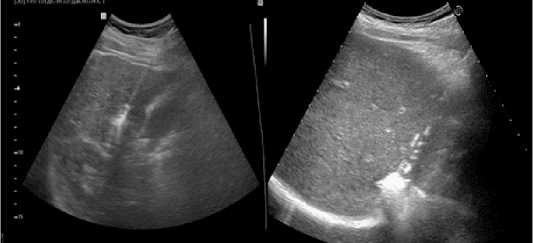

Для радиочастотной абляции применяли аппарат Cool-tip (Covidien, Ирландия) мощностью 200 Вт с набором электродов диаметром 1,2–2,0 мм и длиной 10–25 мм. Время экспозиции варьировало от 4 до 10 минут в зависимости от размера опухоли, температура в очаге достигала 100°C. Для микроволновой абляции использовали системы AveCure MWG881 (MedWaves, США) мощностью 32±2 Вт с частотой 902–928 МГц и Surblate (Vision Medicals, Китай) мощностью 90 Вт с частотой 2,45 ГГц и набором антенн (толщина 14– 16 G, активная зона 2–4 см). Время воздействия составляло 5–10 минут, температура достигала 120°C. Для лазерной абляции применяли систему Echolaser X4, сочетающую УЗ-аппарат и четырёхканальный лазер с длиной волны 1064 нм, мощностью 5,0 Вт и энергией 1800 Дж на волокно. Установку аппликаторов выполняли под УЗ- (рис. 1) или видеолапаро-скопическим контролем при чрескожном чреспеченочном доступе либо интраоперационно во время лапаротомии.

Рис. 1. Выполнение лазерной абляции

Fig. 1. Performing laser ablation

С 2017 года применяли лазерную абляцию на аппарате Echolaser X4. 45 пациентов получили лечение (средний возраст 56,32±2,65 года; 25 мужчин, 20 женщин) с опухолями 1–3,3см. Преимущества: малый диаметр аппликаторов (17– 21G), возможность использования нескольких световодов, абляция множественных метастазов, полная совместимость с МРТ, безопасность при кардиостимуляторах. Метод эффективен в случаях, когда опухоли находятся вблизи крупных сосудов. Риск повреждения сосудов минимизирован в связи с тем, что при выполнении операции формируется небольшая и четкая зона абляции без вовлечения в сосудистые структуры.